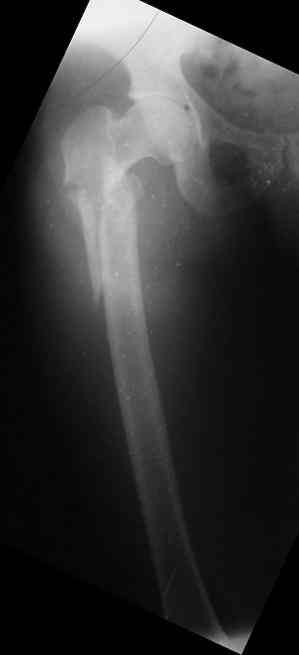

Male, 75 yrs old.

Right hip fracture as an interthrocanteric with extension to diaphysis Tronzo V.

Option for treatment:

1.      DHS

2.      90 - 95 g AO Plate (Condylar Plate)_

3.      Reconstruction Hip Nail

4.      Intertrochanteric Nail System

5.      Externa hip fixator

6.      None of the above.